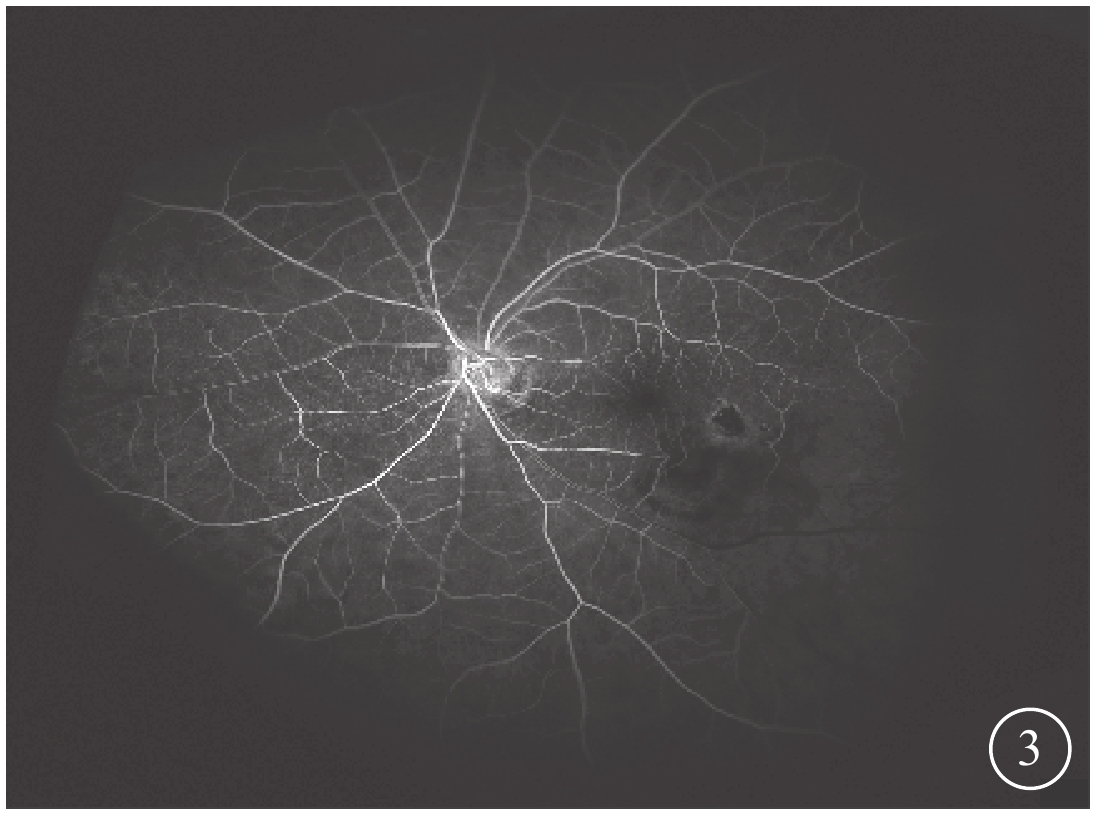

末次隨訪時,患眼BCVA為0.15~0.6,平均BCVA為0.42±0.24。患眼后房型人工晶狀體位正,黃斑部出血吸收。FFA檢查發現,患眼顳下視網膜動脈分支處強熒光點消失(圖3)。OCT檢查發現,患眼黃斑結構逐漸恢復(圖4)。所有患眼均未發生視網膜脫離、黃斑裂孔等并發癥。

圖3

圖1同眼手術后FFA像。顳下視網膜動脈分支處強熒光點消失

圖3

圖1同眼手術后FFA像。顳下視網膜動脈分支處強熒光點消失

末次隨訪時,患眼BCVA為0.15~0.6,平均BCVA為0.42±0.24。患眼后房型人工晶狀體位正,黃斑部出血吸收。FFA檢查發現,患眼顳下視網膜動脈分支處強熒光點消失(圖3)。OCT檢查發現,患眼黃斑結構逐漸恢復(圖4)。所有患眼均未發生視網膜脫離、黃斑裂孔等并發癥。

圖3

圖1同眼手術后FFA像。顳下視網膜動脈分支處強熒光點消失

圖3

圖1同眼手術后FFA像。顳下視網膜動脈分支處強熒光點消失